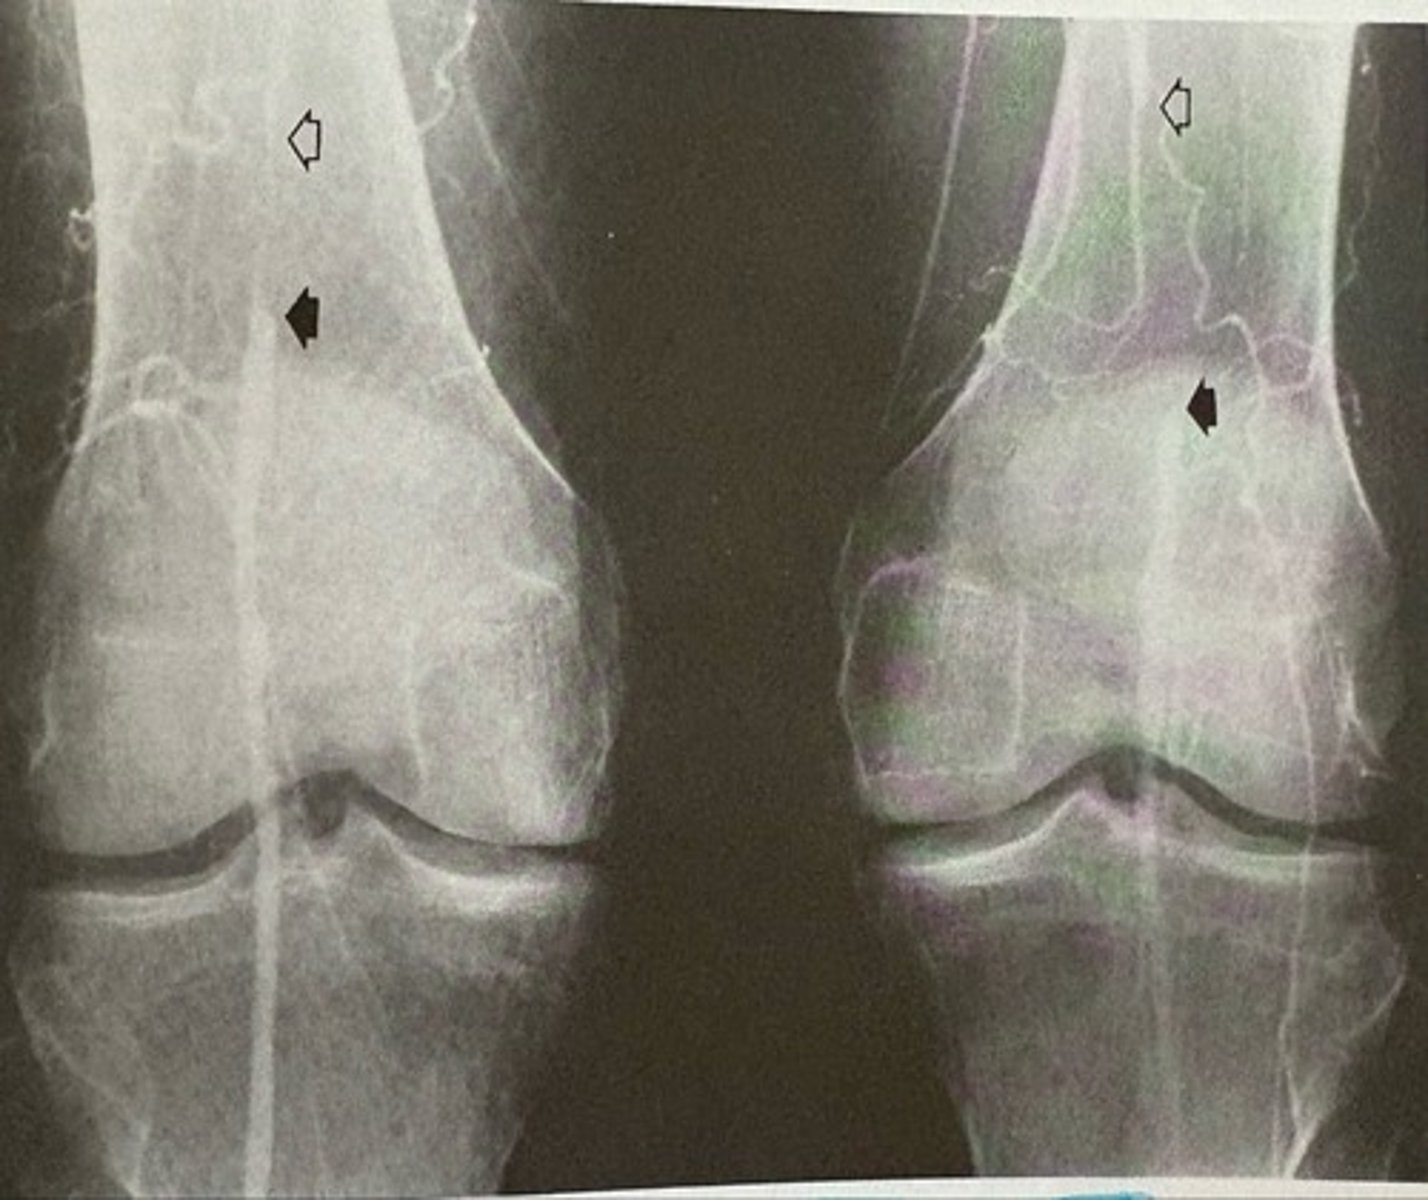

bilateral atherosclerosis of the femoral arteries

what pathology is present?